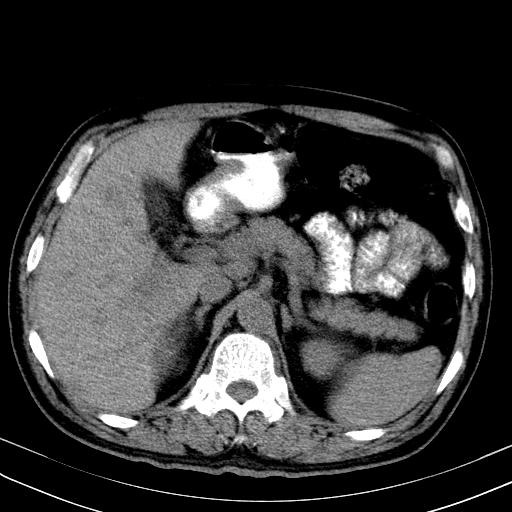

先行ct平扫,纵膈内多发软组织影,ct值约为36hu,以下为增强扫描和腹部平扫。

还见胃窦壁增厚!转移亦有可能!

大家看看肝脏右叶片状低密度影是什么改变啊?

淋巴瘤?肝脏请增强后说啊

多发肿大淋巴结影,肝内改变需结合强化观察